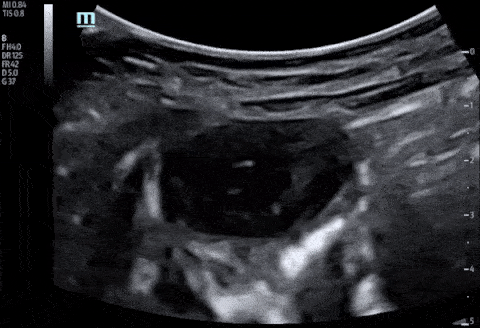

Bowel-GI - Ruptured Appendix with Abscess Formation

A 2 year old F with 1 week of fever, vomiting, diarrhea and abdominal pain presented to the emergency department. A work up was initiated including POCUS of the right lower quadrant which revealed a ruptured appendix with abscess formation. Paul Khalil, MD. Assistant PEM POCUS director at University of Louisville/Norton Children’s @khalil3paul